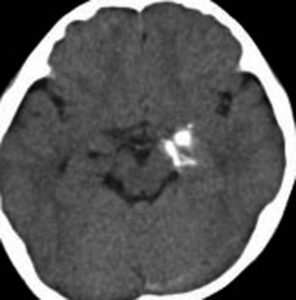

第4室床過誤腫の典型例です

新生児期より動作停止と右眼瞼のちく搦,4ヶ月で右眼の閉眼と口角の引きつれ(顔面けいれん)が目立つようになりました。2歳時には数十秒ごとに発作を繰り返していました。

MRIでは橋の背側(第4脳室床)にT1/T2で等信号の隆起(腫瘤)がみられました。